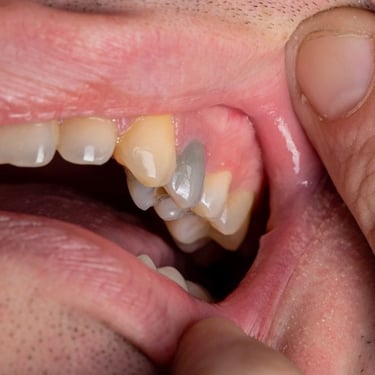

Fractura Radicular Vertical

Una fractura radicular vertical es una fisura que se extiende a lo largo de la raíz del diente, a menudo causada por un trauma o una presión excesiva.

Los pacientes suelen sentir dolor al morder y pueden notar hinchazón.

La fractura generalmente requiere la extracción del diente, ya que es difícil de reparar. Es crucial tratarla rápidamente para evitar infecciones.